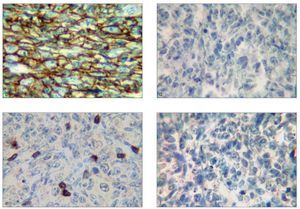

El examen histológico mostró un fuerte infiltrado difuso constituido por células blásticas linfoides grandes que presentaban núcleos ovoides y nucleolos prominentes, con presencia de numerosas mitosis atípicas (figs. 2a y 2b). La inmunohistoquímica mostró células pleomórficas positivas para CD20 y negativas para CD30, CD3, y anticuerpos Alk, confirmando el diagnóstico de LNH difuso de células B grandes (figs. 2c a 2f). Una vez completado el estudio se descartó linfoma sistémico.

Figuras 2c a 2f. Inmunohistoquímica que muestra células pleomórficas difusamente positivas para CD20 (c) y negativas para CD30 (d), CD3 (e) y anticuerpos Alk (f) (inmunoperoxidasa; 40 aumentos originales). En la figura 2e, solo son positivos algunos linfocitos T.